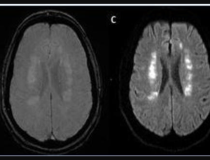

This photo gallery shows the variety of radiological presentations of COVID-19 (SARS-CoV-2) in medical imaging, including computed tomography (CT), radiograph X-rays, ultrasound, echocardiograms and magnetic resonance imaging (MRI). The radiology images show examples of typical COVID pneumonia in the lungs and the numerous complications the virus causes in the body in multiple organs, including the brain, kidneys, heart, abdomen and vascular system.